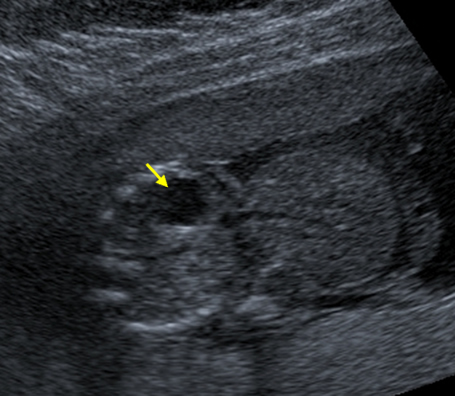

An abdominal wall defect is an abnormal type of hernia either through the cord insertion or by the side of the cord. In this ultrasound image, note the outline of the herniated contents outside the abdomen. The fetal spine and fetal stomach can also be seen.